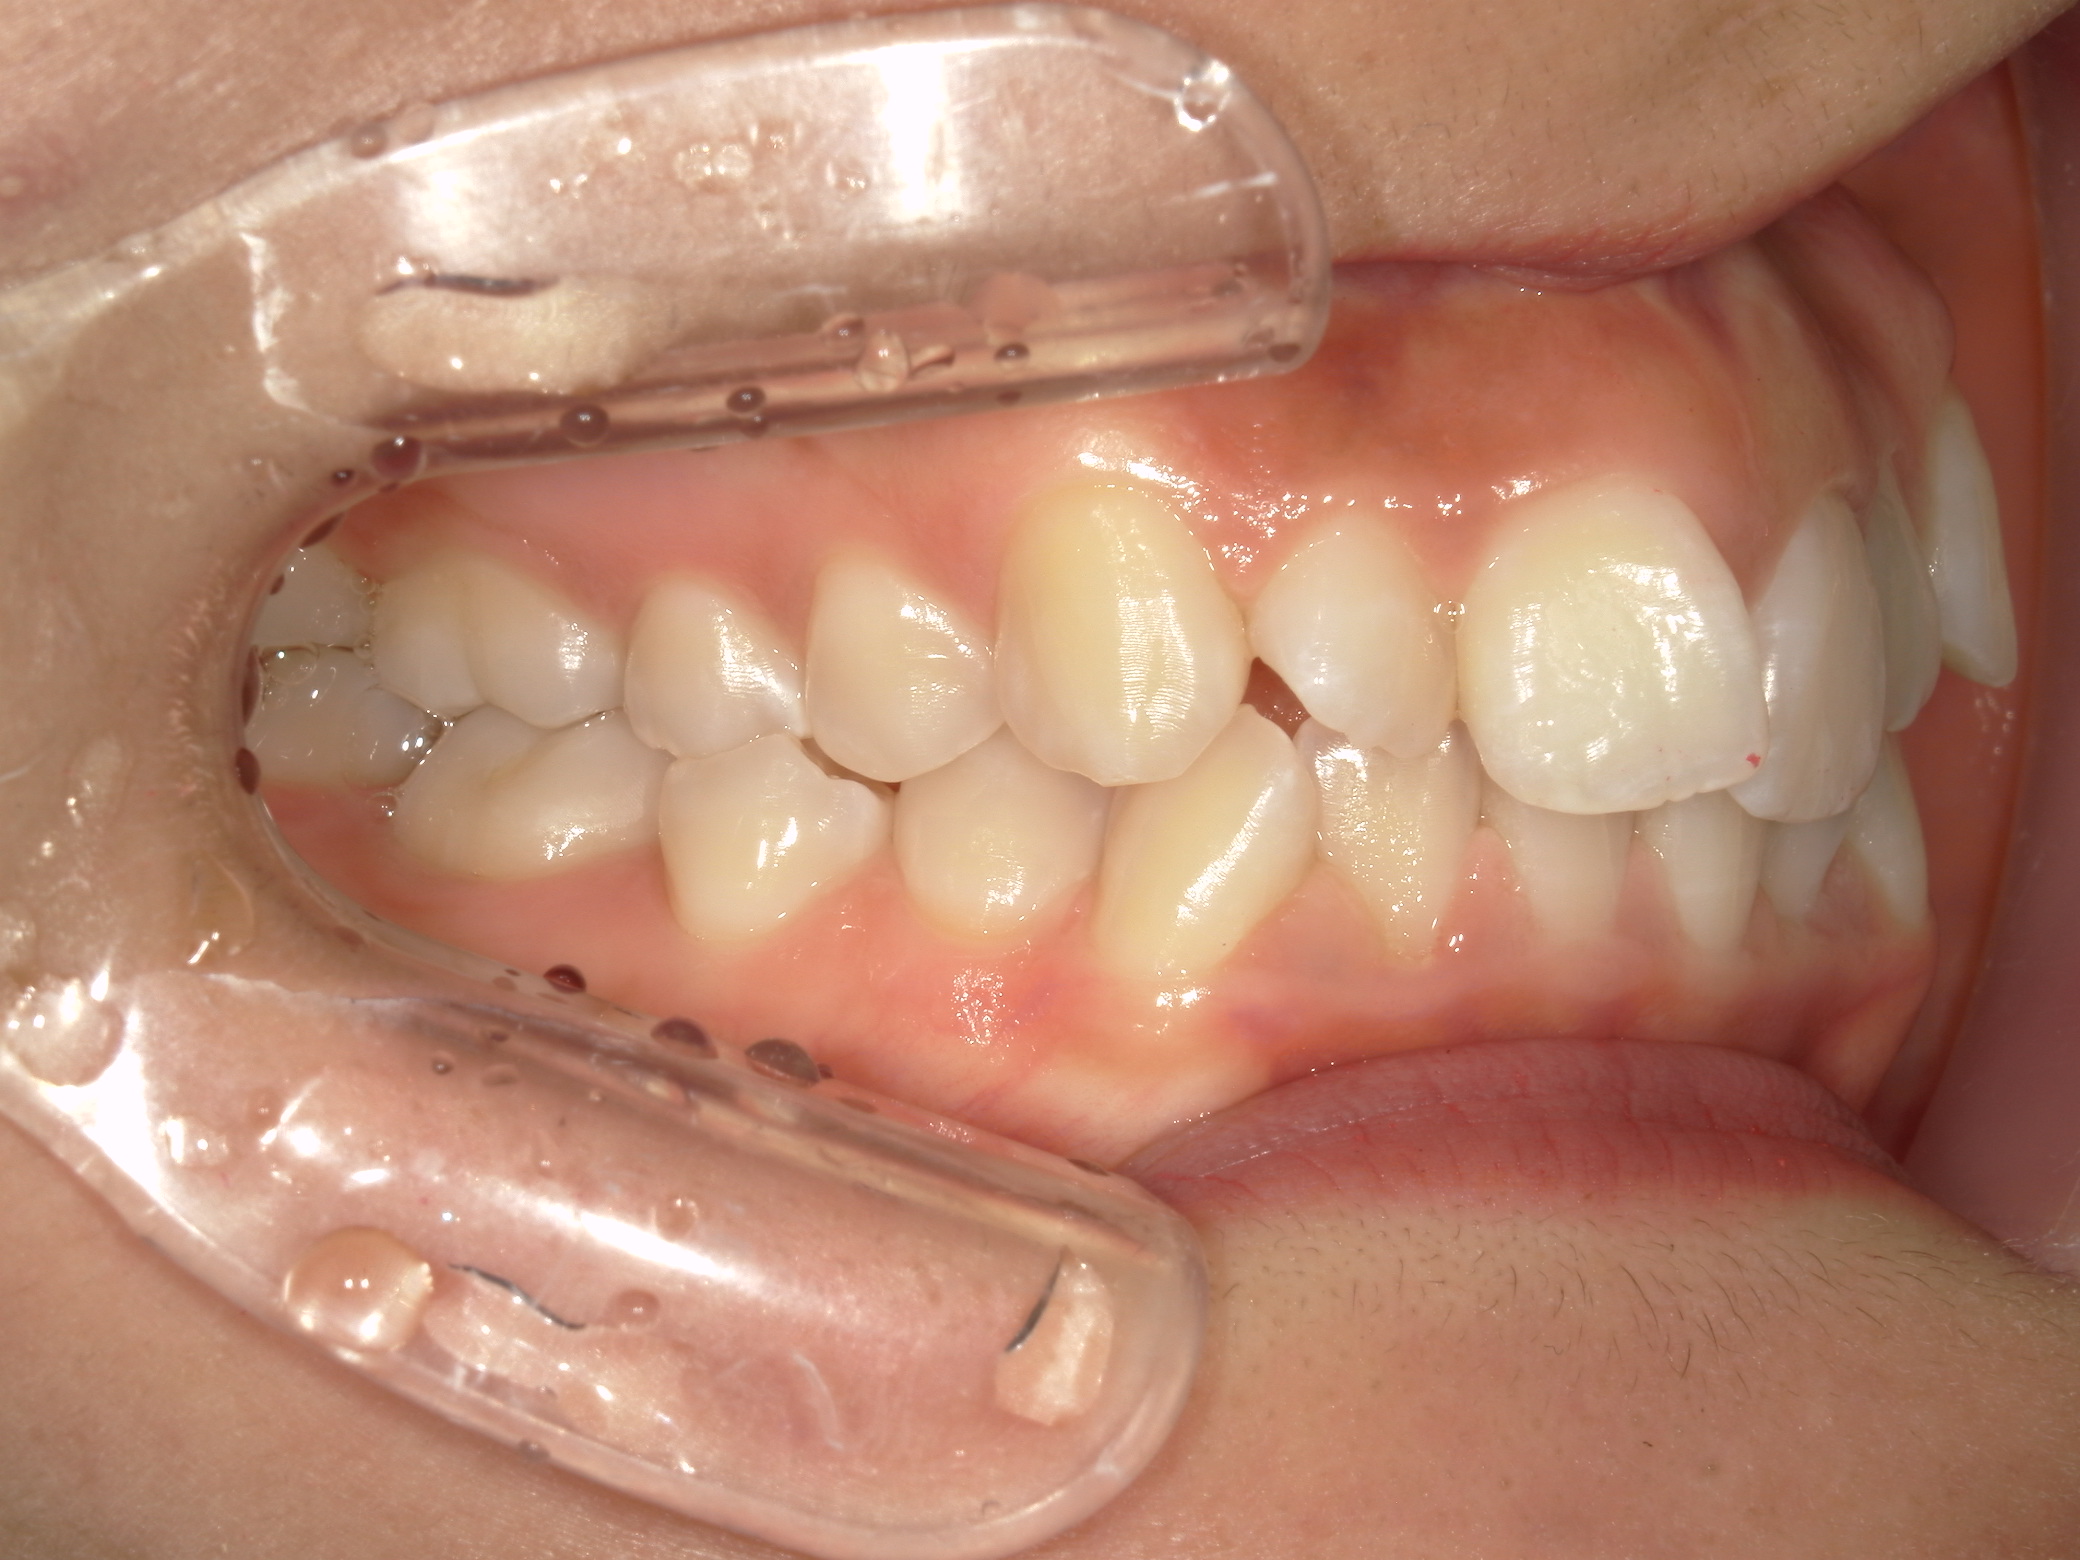

プチワイヤー矯正 症例(54)

ミニインプラント(2本)、スライスカットを併用。

治療の流れ

カテゴリー : ガタガタ(叢生)